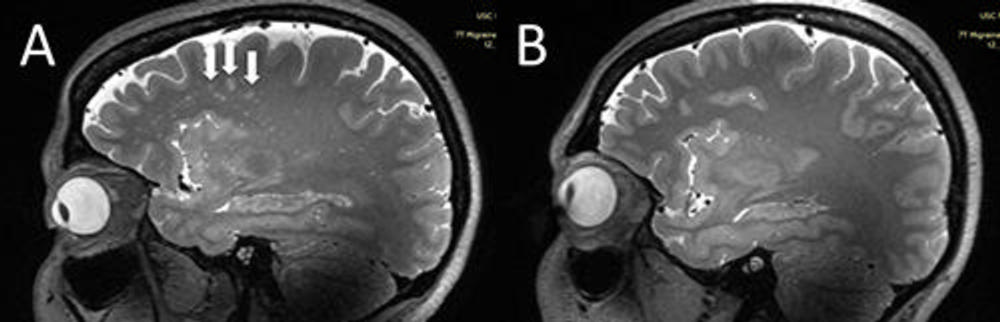

يقول عالم الطب ويلسون شو، من جامعة جنوب كاليفورنيا في لوس أنجلوس: الأشخاص الذين يعانون من الصداع النصفي المزمن والصداع النصفي العرضي؛ يوجد عندهم تغيرات كبيرة في المساحات المحيطة بالأوعية في منطقة دماغية تسمى centrum semovale، وهي المنطقة المركزية للمادة البيضاء في الدماغ الواقعة مباشرة - أسفل القشرة الدماغية، ووظيفة هذه المساحات ليست مفهومة تمامًا، كما لم يتم الوصول إلى هذه التغييرات من قبل.

وكشفت عمليات المسح، أن المساحات المحيطة بالأوعية الدموية في المنطقة الوسطى للمرضى الذين يعانون من الصداع النصفي؛ قد اتسعت بشكل ملحوظ مقارنة بالمجموعة الضابطة.